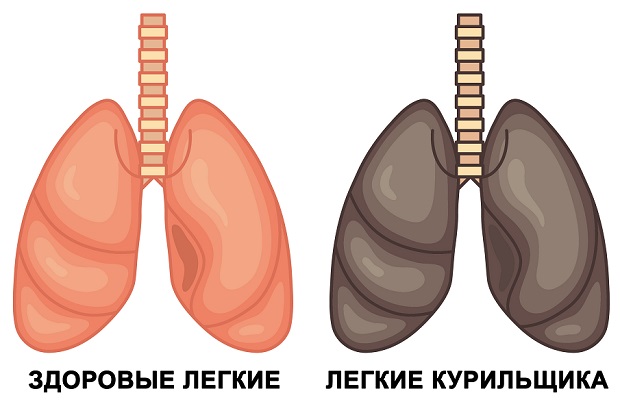

Здоровые Легкие Картинки

Здоровые Легкие Картинки 117 фото